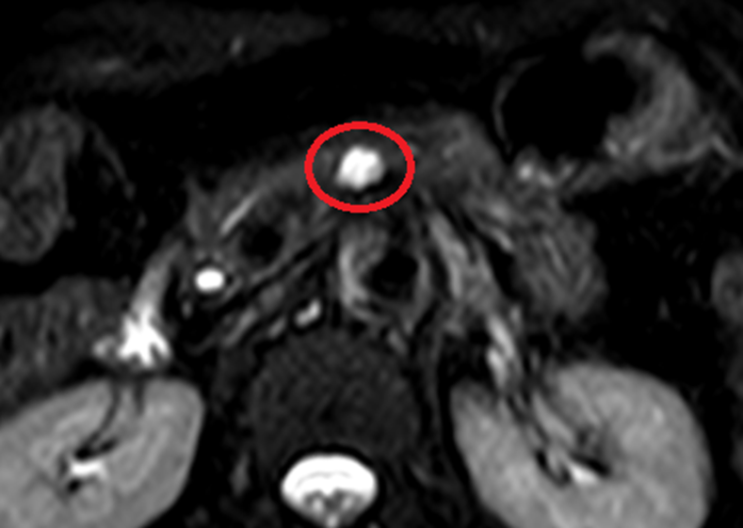

췌장MRI 검사 결과, 췌장몸통 쪽으로 약 1cm 가량의 물혹이 보이고 있으며, 이는 췌장담도와 연결성이 보이고 있습니다. 이에 췌관내유두점액낭종으로 생각이 되며, 이에 대해서 추가적인 치료를 위해 상급병원에 진료의뢰드렸습니다.

• 췌장MRI: 췌장담도와 연결성 확인(빨간 동그라미) 췌장MRI: 췌장담도와 연결성 확인(빨간 동그라미)